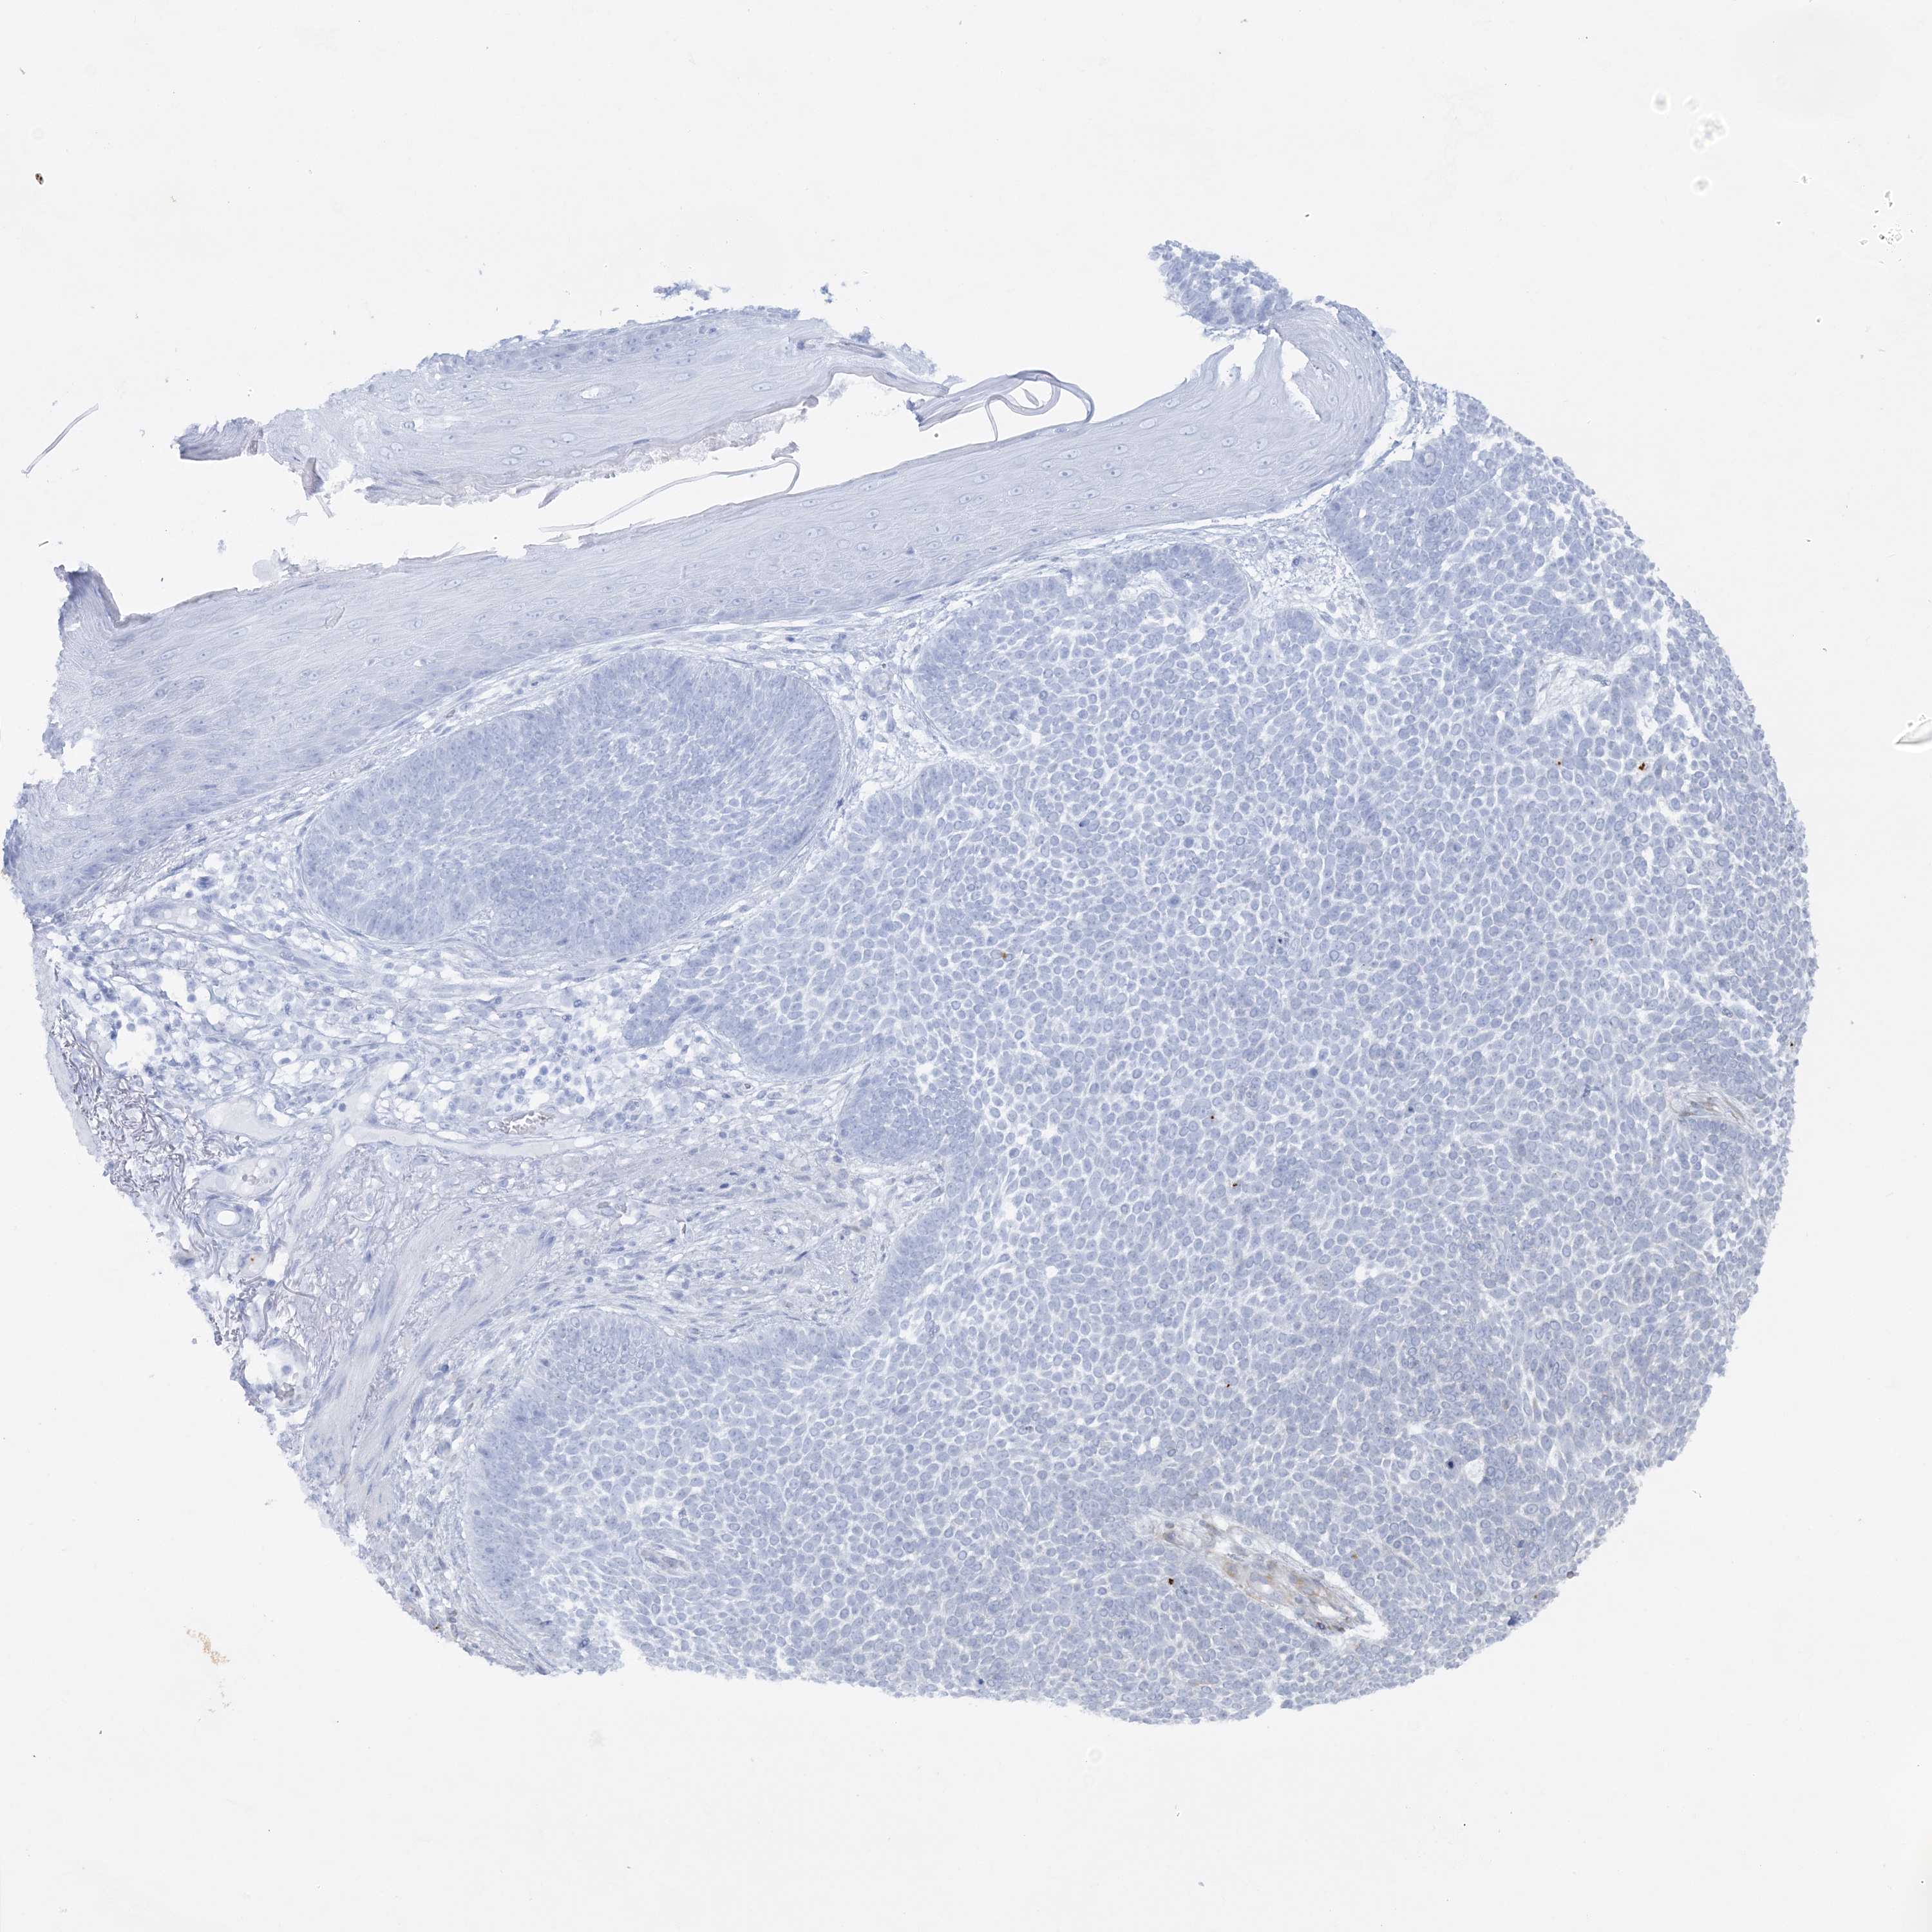

Basal cell and squamous cell cancer

SKIN CANCER - Protein expressioni

A mouse-over function shows sample information and annotation data. Click on an image to view it in a full screen mode. Samples can be filtered based on level of antibody staining by selecting one or several of the following categories: high, medium, low and not detected. The assay and annotation is described here.

Each image is clickable and will lead to virtual microscopy that enables deeper exploration of all samples and also displays staining intensity scores, fraction scores and subcellular localization as well as patient and tissue information for each sample.

Antibody HPA036560

Antibody HPA036561

Basal cell carcinoma

Squamous cell carcinoma, NOS

Squamous cell carcinoma, metastatic, NOS